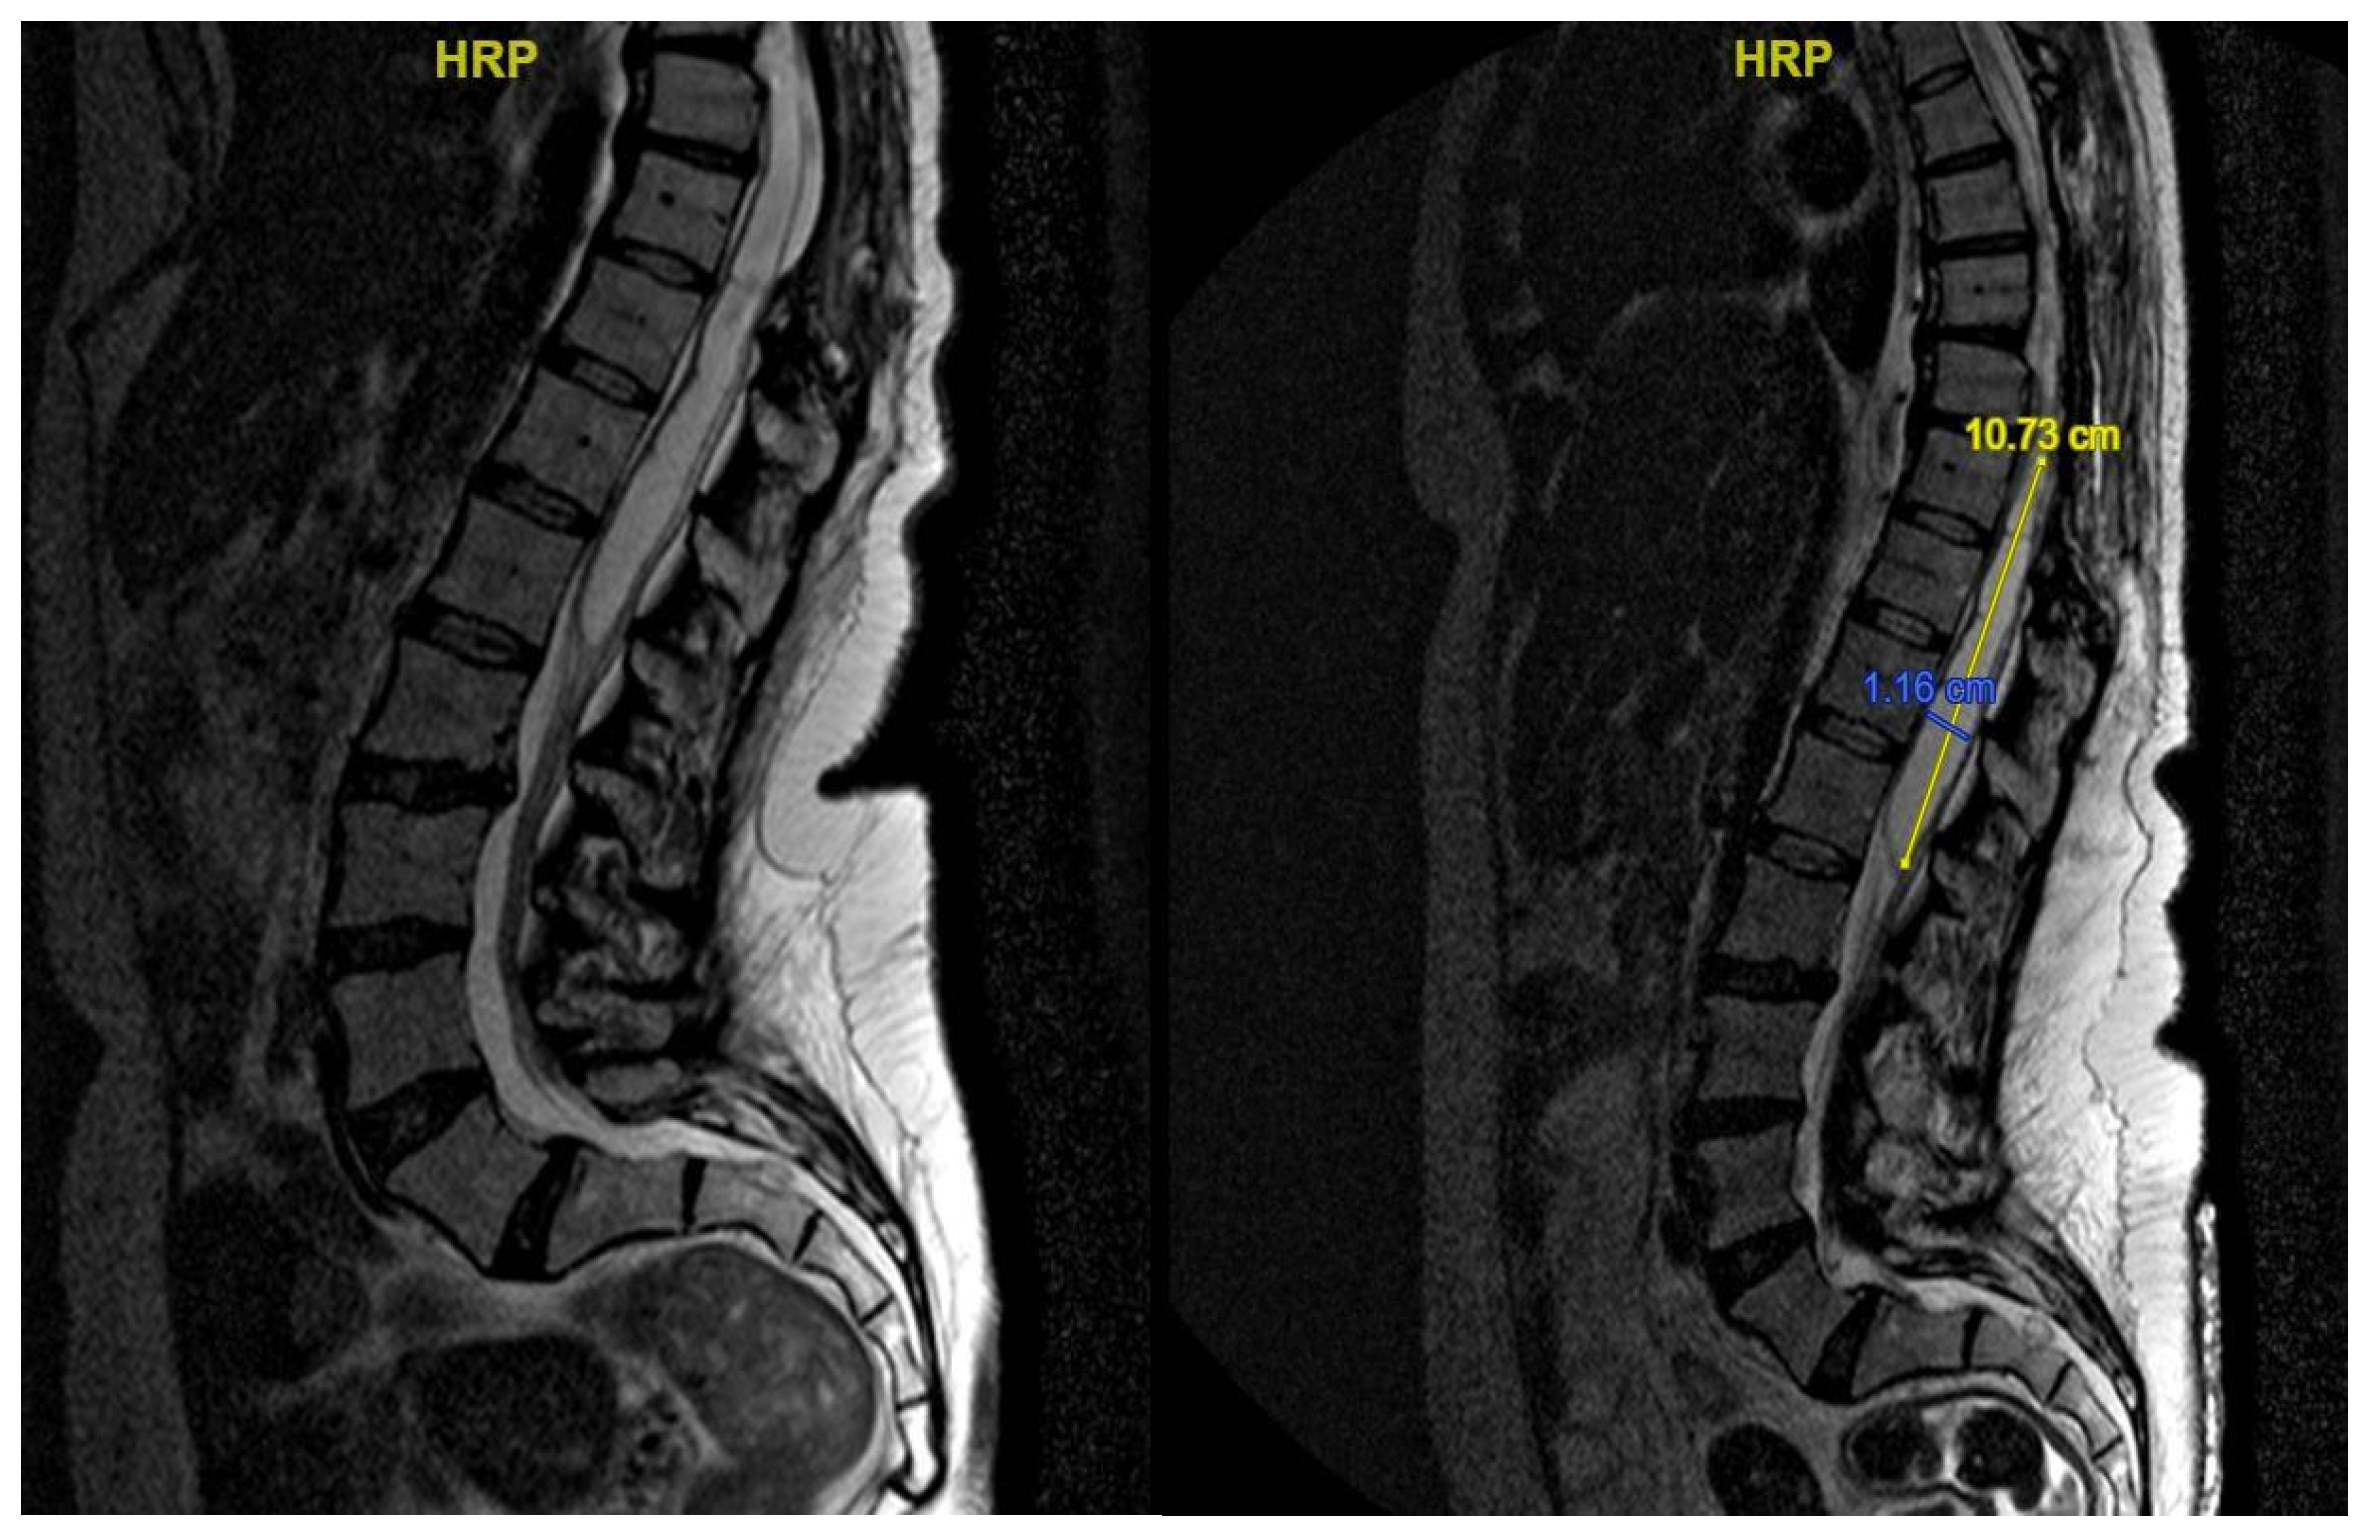

3.4.2. Case 2

| Level | T12–L2 | C5–C6 | T7–T10 | T8–T9 | T8–T11 |

| Location | Intramedullary | Intradural | Intradural–Extradural | Intramedullary | Intradural |

| Surgical treatment | lysis of adherences and syrinx cavity opening | resection of the cystic formation and adhesiolysis | resection of the cystic formation and adhesiolysis | resection of the cystic formation and adhesiolysis | resection of the cystic formation and adhesiolysis |

| Complications | CSF fistula | infection | None | CSF fistula | None |

| KPS pre-op (%) | 70 | 50 | 70 | 80 | 90 |

| KPS post-op (%) | 80 | 50 | 60 | 90 | 80 |

| ASIA score pre-op | C | B | B | C | D |

| ASIA score post-op | D | B | C | C | D |